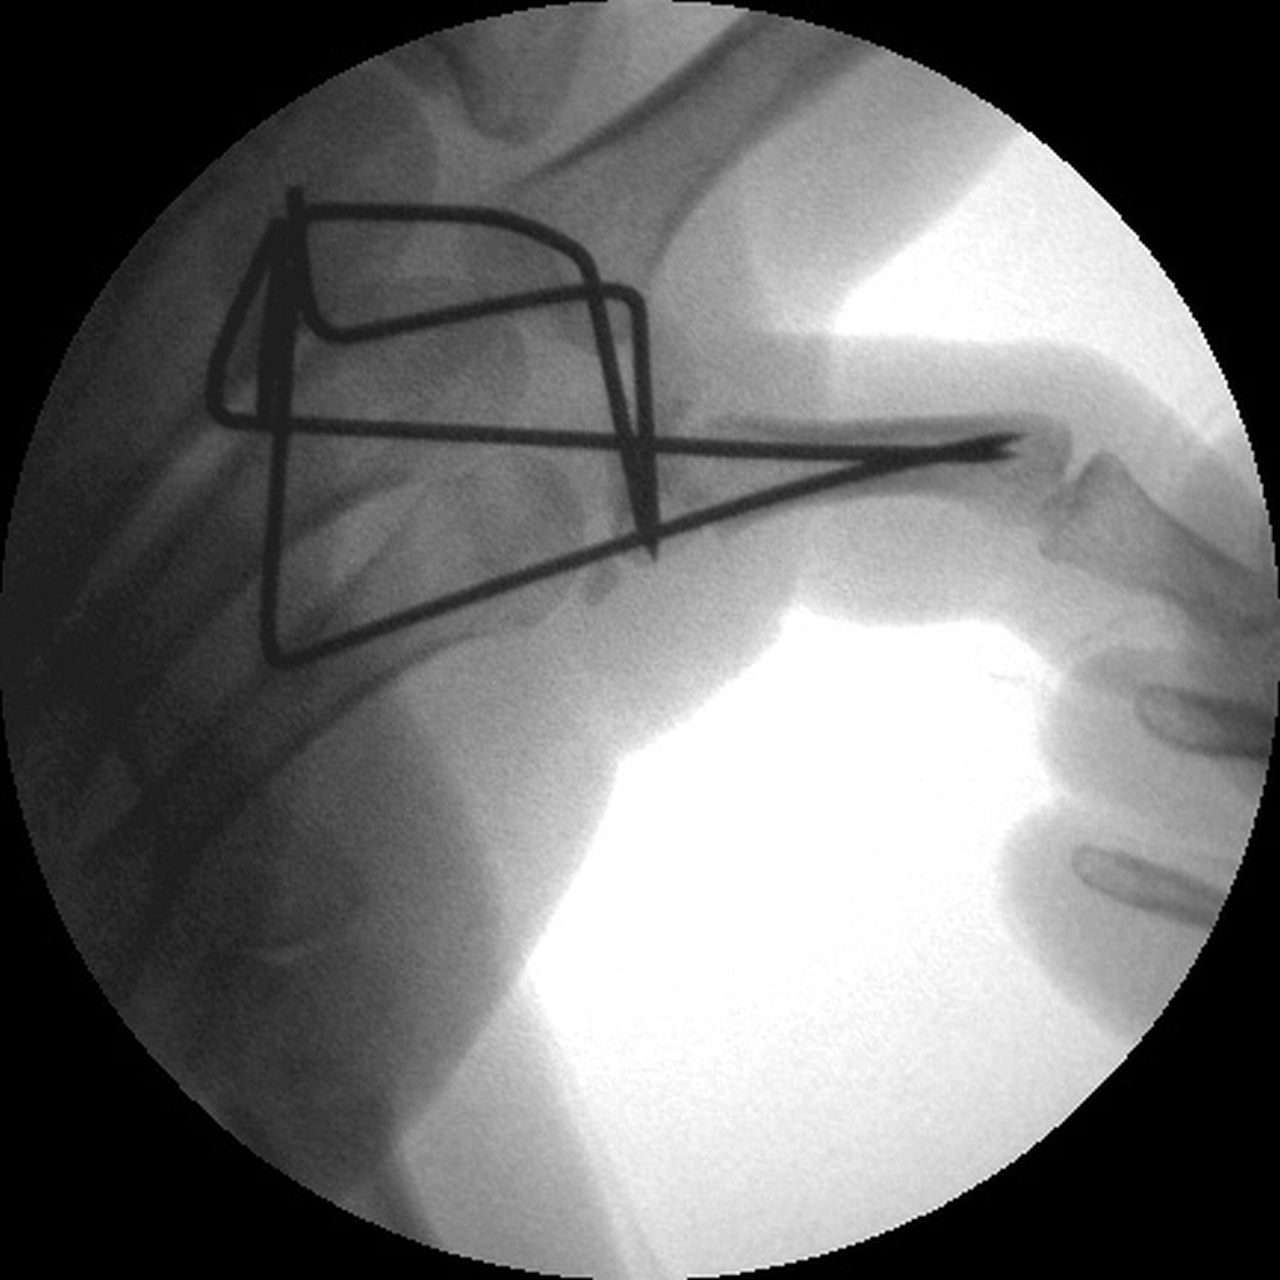

| Intraoperative

fluoroscopy. |

| Manipulation and closed reduction: |

| Percutaneous pins placed across the fracture line and also dorsal to palmar into the proximal fracture fragment. |